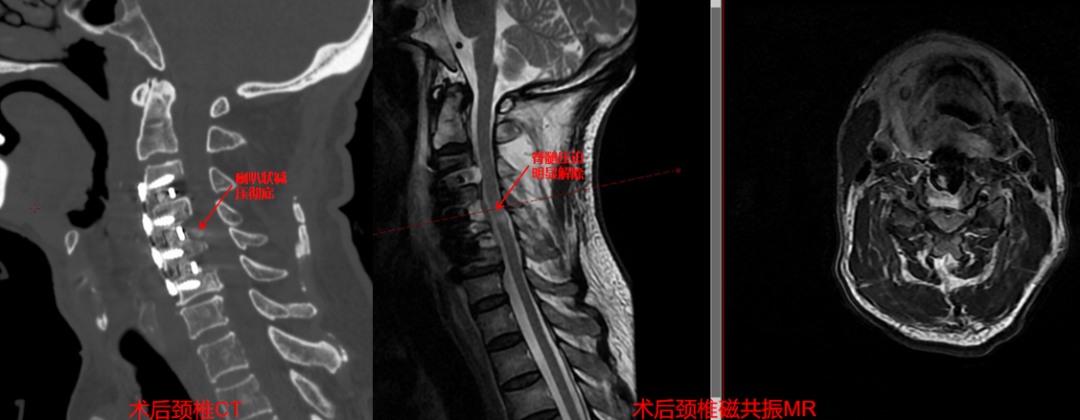

术后第 3 天复查颈椎 CT+磁共振显示:椎管减压精准且彻底,颈 3-颈 5 脊髓压迫彻底解除、硬脊膜膨隆良好,内固定位置满意。